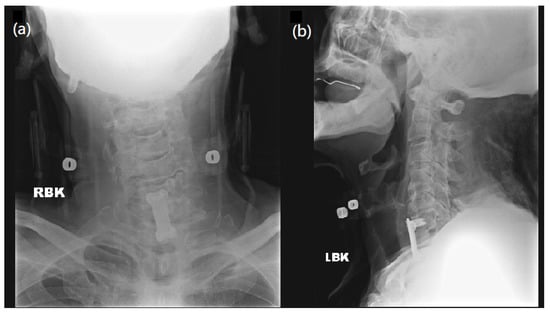

However, two weeks after surgery, his muscle strength of bilateral lower limbs suddenly diminished to grade 3/5 and continued to worsen. A neurologist was consulted to explore the causes of muscle weakness and a series of examinations were made to explore possible conditions, such as electrolyte imbalance, surgical issue of cervical spine, lumbar spine problem, or intracranial lesion. He had no medical history of a gastrointestinal tract infection or respiratory infection before or after the cervical surgery. While laboratory tests (Table S1) and microbiology studies showed unremarkable findings, ongoing infection was also excluded. Image studies (Figure 2 and Figure 3) indicated no instrumental backout, no new onset of spine stenosis, or intracerebral hemorrhage. A lumbar puncture was then performed under the suspicion of GBS. CSF studies revealed albuminocytologic dissociation, including increased protein levels (167 mg/dL) and an absence of WBC. Blood tests showed normal electrolyte balance (Table S1).

Figure 2. Postoperative radiography over C spine. (a) AP view and (b) Lateral view of C spine radiography demonstrates disc space narrowing over C4-5, C5-6, C6-7, and degenerative change plus anterior osteophyte formation, with cervical spine locking plates and screws over C6-T1, with no sign of instrumentation backout.